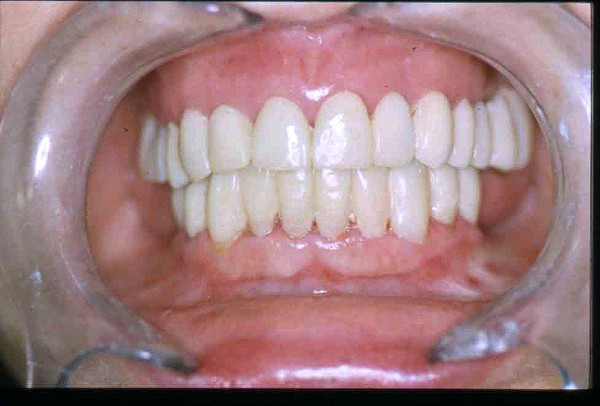

APRECIACIONES DIAGNÓSTICAS EN BASE A LA APERTURA MENTAL DEL CLÍNICO FRENTE A LO QUE EL PACIENTE PROPONE EN MUCHAS OCASIONES , LA DEMANDA DE LOS PACIENTES NOS INCLINAN A FOCALIZAR NUESTRA ATENCIÓN EN LAS PIEZAS DE LAS CUALES EL ENFERMO SE QUEJA. PACIENTE SEXO FEMENINO, 55 AÑOS, SE PRESENTA A LA CONSULTA DERIVADA POR COMPAÑERO GENERALISTA, QUIEN LLEVA MESES PROCEDIENDO A LA «DESINFECCIÓN» DE UN PRIMER PREMOLAR IZQUIERDO, EL QUE SE PRESENTA ABIERTO EN SU CONDUCTO EN EL AFÁN DE PERMITIR EL ESCAPE DE GASES DE UNA GANGRENA PULPAR. A LA INSPECCIÓN CLÍNICA SE OBSERVAN FACETAS PARAFUNCIONALES DE TERCER GRADO , ASINTOMÁTICAS, CON EVIDENTES DIFICULTADES MASTICATORIAS Y ESTÉTICAS , FALTA TOTAL DE SUS MOLARES INFERIORES, Y ADELANTAMIENTO PRONUNCIADO DE SU MANDIBULA, LA QUE CUESTA MANIPULAR DEBIDO A LA SITUACIÓN DE ESPASMO DE CASI TODA SU MUSCULATURA GNATICA. SE ESTUDIA EL CASO RADIOLOGICAMENTE, Y SE RELAJA EL SISTEMA MEDIANTE LAM. DE LONG REALIZANDO UN MONTAJE EN LA ORC OBTENIDA. NO SATISFECHOS CON EL RESULTADO, CONFECCIONAMOS UN JIG DE LUCIA, EL QUE DEJAMOS EN BOCA TODA UNA NOCHE, AL CABO DE LA CUAL REALIZAMOS UN NUEVO REGISTRO REALIZAMOS UN ENCERADO RÁPIDO DEL CASO, Y CONFECCIONAMOS UNA ESTRUCTURA OCLUSAL PLASTICA, QUE ADEMÁS REPONGA EL ASPECTO ESTÉTICO PERDIDO (FÉRULA DE RELAJACIÓN DE COMPONENTE ESTÉTICO), LO QUE PERMITE AL ENFERMO LUEGO DE DOS DÍAS DE USO, NO SOLO CORROBORAR LA COMODIDAD MASTICATORIA Y LA FALTA DE SÍNTOMAS MUSCULARES, SINO TAMBIÉN OBSERVAR APROXIMADAMENTE LA DIFERENCIA ENTRE LA SITUACIÓN INICIAL Y LO QUE PUEDE LOGRARSE MEDIANTE EL TRATAMIENTO. EL PACIENTE ADVIERTE LA MEJORÍA DE LA SITUACIÓN. ACEPTADO POR PARTE DEL MISMO EL TRATAMIENTO SUGERIDO, CREAMOS UN JUEGO COMPLETO DE PROVISORIOS EN BASE AL ENCERADO, Y PROCEDEMOS A TRATAR LA INFRAESTRUCTURA, QUE CONSISTE EN LAS ENDODONCIAS, SUS REFUERZOS A PERNOS DE ORO, LOS ASPECTOS PERIODONTALES DEL CASO, Y DOS IMPLANTES INFERIORES CON TÉCNICA SEMISUMERGIDA ,DE 5 MM DE ANCHO POR 12 DE LONGITUD, CON ANILLO DE ZIRCONIO , A LA ESPERA DE OSTEOINTEGRACIÓN, TRANSCURREN TRES MESES EN EL USO DE UNA NUEVA OCLUSIÓN CONSTITUIDA POR LOS PROVISIONALES, SEGÚN EL ENCERADO, QUE SE REALIZÓ SIGUIENDO LOS CÁNONES DE UNA OCLUSIÓN ORGÁNICA. COMPROBADA LA EFICACIA DE LA NUEVA SITUACIÓN, CON SUS DISCLUSIONES LATERALES Y POSTERO ANTERIORES CORRECTAS, CARECIENDO YA DE SINTOMATOLOGÍA MUSCULAR (SIN MIALGIAS, SIN MIOSITIS, Y CON UN GRADO DE APERTURA DE 4,50 CM), Y SIN SIGNOS EVIDENTES DE DESGASTE SOBRE EL MATERIAL DE LOS PROVISORIOS, ES DECIR: VERIFICANDO QUE EL PACIENTE YA NO BRUXA, VERTICALIZANDO EL CICLO MASTICATORIO /OTORGANDO ORC/ DIMENSIÓN VERTICAL /PROTEGIENDO A LAS PIEZAS `POSTERIORES DE IMPACTOS LATERALES RECIEN ENTONCES , MONTAMOS EN ARTICULADOR SEMI AJUSTABLE LOS MODELOS DE TRABAJO DEFINITIVOS. CONFECCIONAMOS ENTONCES LAS COFIAS INFRA PORCELANA, EN PORCELANA DE ALTA DENSIDAD EN EL SECTOR ANTERIOR Y EN ORO GALVÁNICO PARA EL SECTOR POSTERIOR PARA LUEGO COMPLETAR LA GUIA ANTERIOR , VERIFICANDO LA ALTURA DE LOS INFERIORES RESPECTO DEL LABIO INFERIOR Y CORROBORANDO LOS PUNTOS DE CONTACTOS INTER CANINOS, QUE CENTRALIZAN LA MANDIBULA Y VERTICALIZAN EL CICLO MASTICATORIO Y LAS DISCLUSIONES CANINAS QUE OTORGARÁN PROTECCIÓN A LOS SECTORES POSTERIORES. POSTERIORMENTE CHEQUEAMOS LA DISCLUSIÓN EN PROPULSIVA DE LA GUIA ANTERIOR YA TERMINADA. FIG38 FIG39 UNA VEZ OBTENIDO UN COMANDO ANTERIOR EFECTIVO, COMO LO ES LA GUIA ANTERIOR CON TODOS SUS COMPONENTES, PROCEDEMOS A REALIZAR LAS TABLAS PREMOLAR / MOLAR DE AMBOS LADOS Y OBSERVAMOS QUE LOS PUNTOS INTEROCLUSALES DE CONTACTO SEAN SUFICIENTES Y CUMPLAN SU OBJETIVO DE OTORGAR ESTABILIDAD MESIO DISTAL Y VESTÍBULO LINGUAL. TRANSCURRIDO UN AÑO DE FINALIZADO EL TRATAMIENTO, REALIZAMOS UN CHEQUEO POST OPERATORIO DEL CASO, EN TODOS LOS PARÁMETROS ANTERIORMENTE MENCIONADOS, Y OBSERVAMOS LA ABSOLUTA ESTABILIDAD DEL MISMO EN TODOS SUS NIVELES Y TEJIDOS.